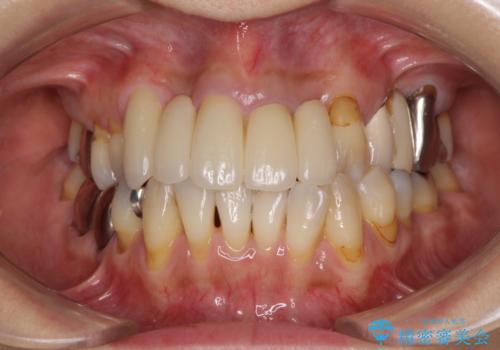

露出していた歯根や金属の縁が見えてしまい、なかなか口を開けて笑うことができなかったのですが、歯肉の位置に縁を合わせることで自然な仕上がりとなりました。

ブリッジの隙間にものが詰まったり、空気が抜けたりすることも無くなり、話しやすさも改善することができました。

露出していた歯根が覆われるため、歯冠が長く見えてしまうことが懸念されましたが特に気になることはなく、患者様には大変満足していただきました。